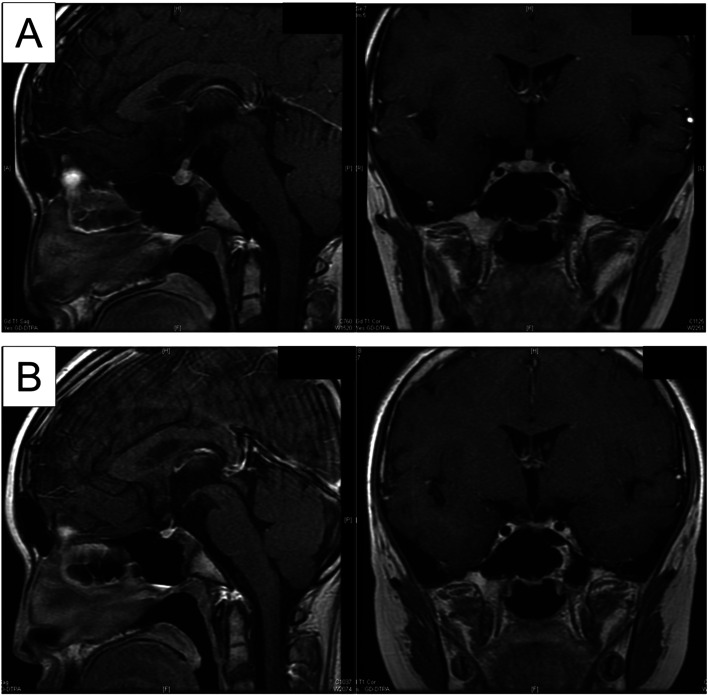

Hypothalamic-pituitary Langerhans cell histiocytosis (HP-LCH) is often associated with arginine vasopressin deficiency (AVD). Patients with AVD caused by HP-LCH rarely develop an impaired osmotic threshold for thirst (OTT). Improvement in OTT among such patients has not been reported in the literature. To our knowledge, here we report the first case of AVD due to HP-LCH in which hypodipsia resolved during chemotherapy. A nine-year-old Japanese girl presented with polydipsia, polyuria, anorexia, and hypernatremia (149.8 mEq/L) and was diagnosed with AVD secondary to HP-LCH. Visual analog scale examination showed a reduced OTT following the water deprivation test. During chemotherapy for Langerhans cell histiocytosis (LCH), serum sodium concentrations became stable between 138.9 and 142.9 mEq/L under the replacement of desmopressin. Repeated visual analog scale examinations showed that she experienced a sense of thirst at a serum sodium concentration of 142.3-144.6 mEq/L, at which she did not experience any thirst prior to the initiation of chemotherapy. These data suggest that chemotherapy directly improved the OTT in our patient. Improved mechanical compression or infiltration of the hypothalamus related to OTT may lead to the recovery of the sense of thirst. This report highlights the potential role of chemotherapy for solitary HP-LCH in patients with hypodipsia and AVD.